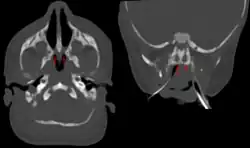

| Bilateral membranous choanal atresia in CT scan | |

Diagnosis is confirmed using CT scan.[1]This is also useful for differential diagnosis.[1]